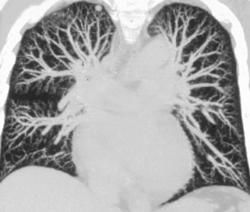

Coronary Calcification in the LAD